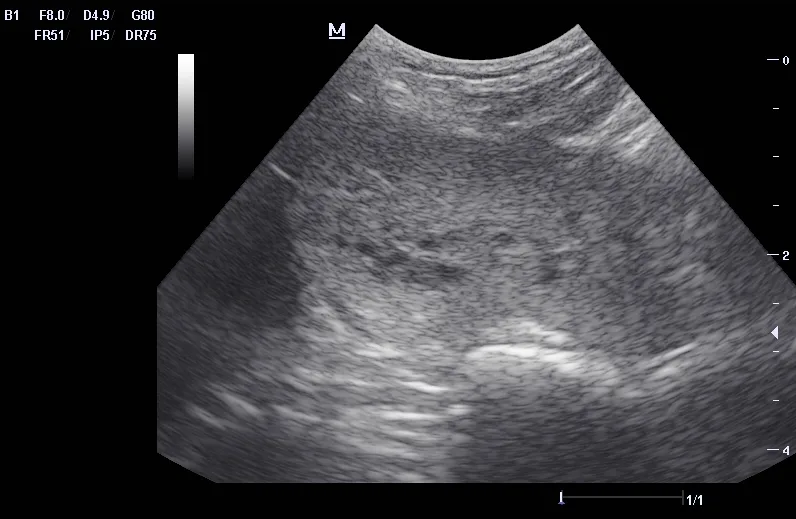

Ultrasound can be useful in evaluating the size, contour, and internal architecture of the prostate. A normal prostate appears homogeneous (Figure 1). The prostate becomes heteroechoic as a result of inflammation, hyperplasia, and neoplasia (Figure 2). The prostatic parenchyma can be focally or diffusely hypoechoic in cases of acute prostatitis or prostatic abscessation (Figure 3), as well as hyperechoic in cases of chronic prostatitis (Figure 4).

Ultrasound image of a prostatic abscess.

FIGURE 3

Prostatic abscess with a focal hypoechoic area